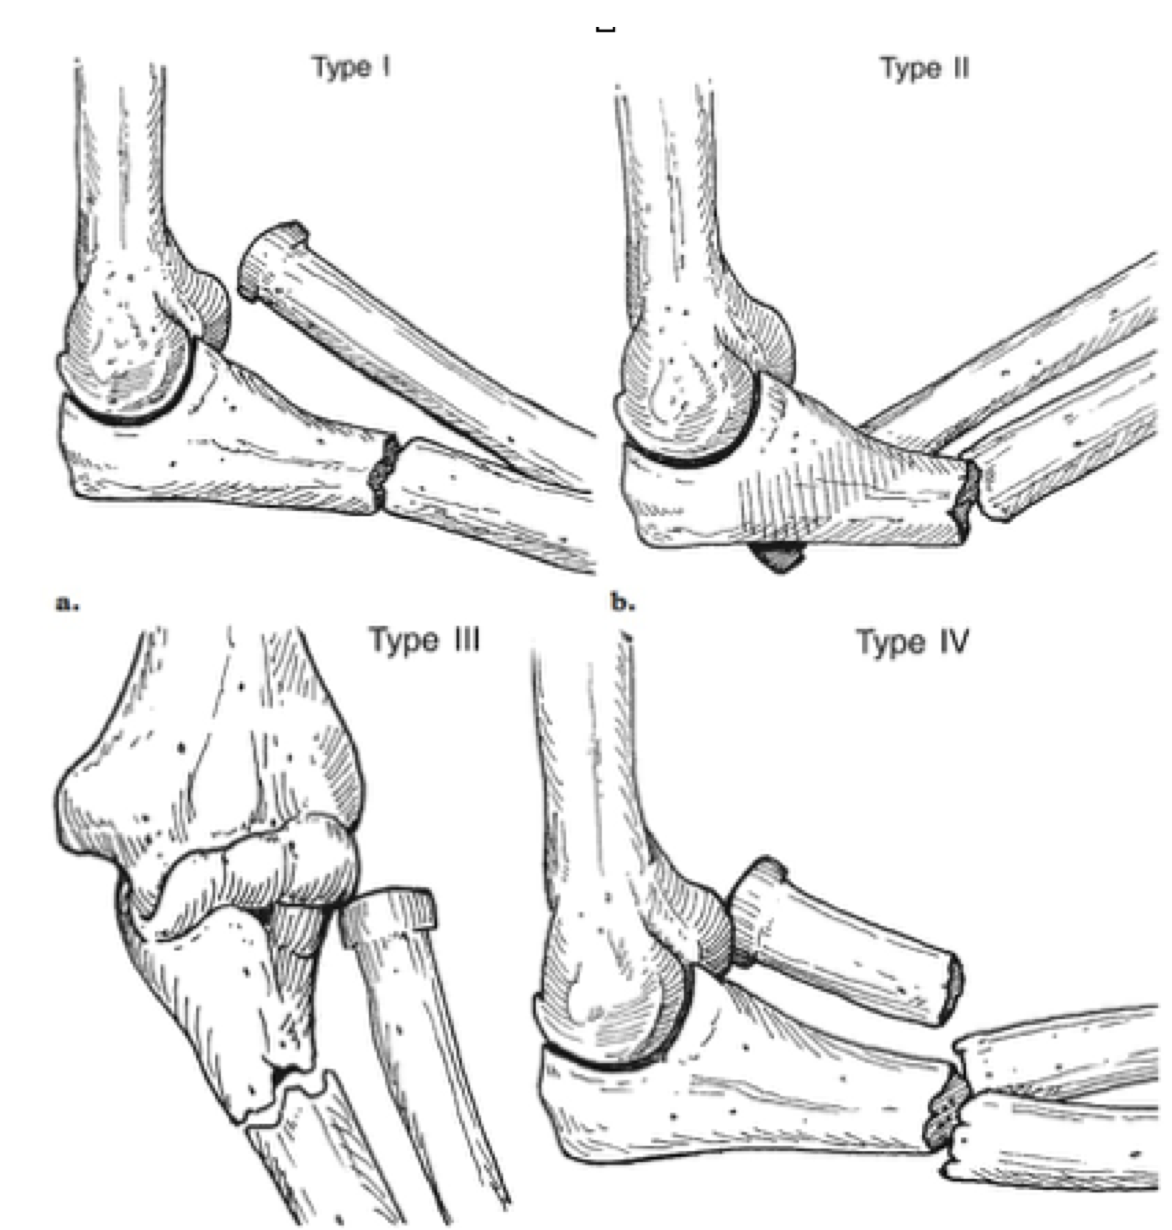

Clasificación de Mason, en que se basa?

• Desplazamiento de las fracturas de cabeza radial

Clasificación de Mason:

• grado 1: cuello o fractura intraarticular de la cabeza radial sin desplazamiento

• grado 2: cuello o fractura intraarticular de la cabeza radial con ligero desplazamiento (>2mm, 30% de la cabeza)

• grado 3: cuello o fractura intraarticular de la cabeza radial completamente desplazada y multifragmentada (no reparables)

Clasificación de Monteggia

I: angulación anterior del apex del radio con fractura del cúbito medial o proximal –> niños

II: angulación posterior del apex del radio “ “ –> adultos

III: Angulación lateral “ “ “

IV: Sin angulación + fractura del radio “ “ “